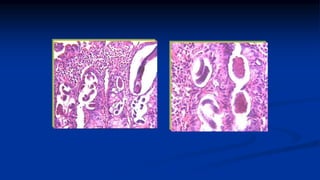

Invasión de mucosa y submucosa intestinal (Duodeno y yeyuno)

 Hembra parásita: Submucosa intestino